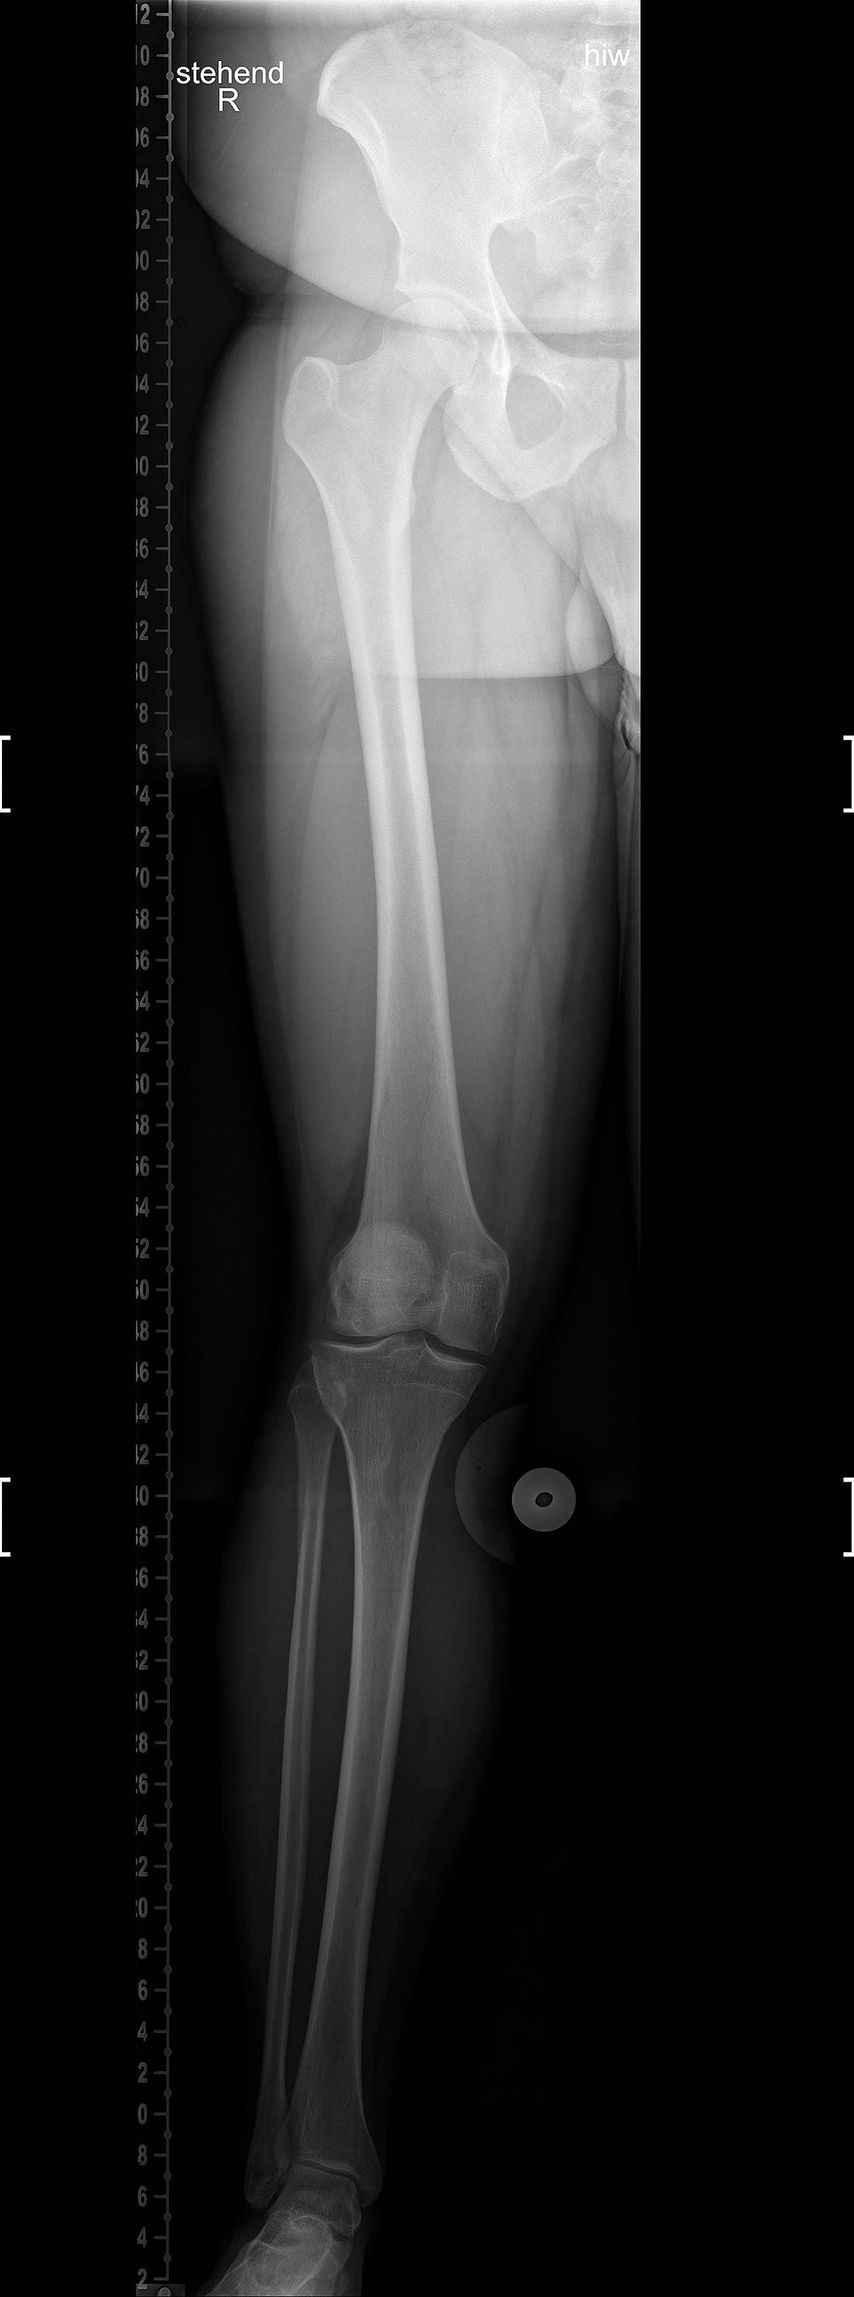

23-jähriger Patient mit wiederkehrenden Patellaluxationen und vermehrtem Valgus von ca. 6,5% (Abb. 6) und einer Trochleadysplasie

Geplant wurde eine lateral aufklappende Femurosteotomie (Abb. 7) mit offener Trochleaplastik und MPFL-Plastik. Bei der Umstellung kam es zu einer iatrogenen Verletzung der A. poplitea. Diese musste durch einen Gefäßchirurgen mit einem Venenbypass (Vena saphena magna) behandelt werden, zusätzlich wurden die Unterschenkelkompartimente gespalten (Abb. 8).

Abb. 8: Zustand nach iatrogener Verletzung der A. poplitea mit Venenbypass und Kompartimentspaltung